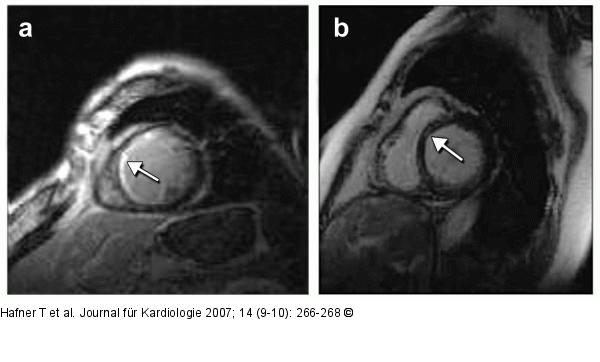

Abbildung 1a-b: Dilatative CMP (a) Dilatative CMP mit ischämietypischem "late enhancement": subendokardiales "late enhancement" im Bereich des Septums (Pfeil); Patient mit koronarer Dreigefäßerkrankung. (b) Dilatative CMP mit nicht- ischämietypischem "late enhancement": streifenförmiges, intramurales "late enhancement" im Bereich des Septums (Pfeil); Patientin nach Myokarditis. |

Abbildung 1a-b: Dilatative CMP

(a) Dilatative CMP mit ischämietypischem "late enhancement": subendokardiales "late enhancement" im Bereich des Septums (Pfeil); Patient mit koronarer Dreigefäßerkrankung. (b) Dilatative CMP mit nicht- ischämietypischem "late enhancement": streifenförmiges, intramurales "late enhancement" im Bereich des Septums (Pfeil); Patientin nach Myokarditis. |